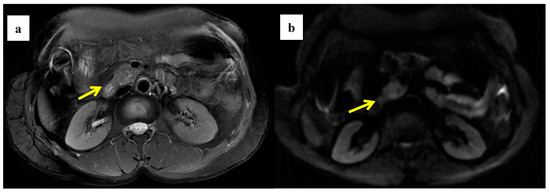

Figure 4.

A 58-year-old woman was found to have a tumor with a head size of about 2.2 cm in the pancreas, which was pathologically confirmed to be pancreatic ductal adenocarcinoma after surgery; we found that the tumor was characterized by a high ADC value, high D value, and low f value after quantitative MRI measurement. She survived for 61 months without recurrence after surgery. MRI T2 (a); DWI (b); and ADC map (c) showed solid mass in the head of pancreas with measured ADC of 1.59 × 10−3 mm2/s, D value of 1.41 × 10−3 mm2/s, and f value of 0.18. Immunohistochemical staining showed that a few cancer-associated fibroblasts (CAFs) were present in the stroma ((d) α-SMA, ×10), carcinoma cells weakly expressed VEGF in the cytoplasm ((e) VEGF, ×10), and carcinoma cells showed weak immunoreaction of anti-HIF-1a in the nuclear((f) HIF-1α, ×20). These findings suggested that the tumor microenvironment was relatively quiet with a lower hypoxia level.